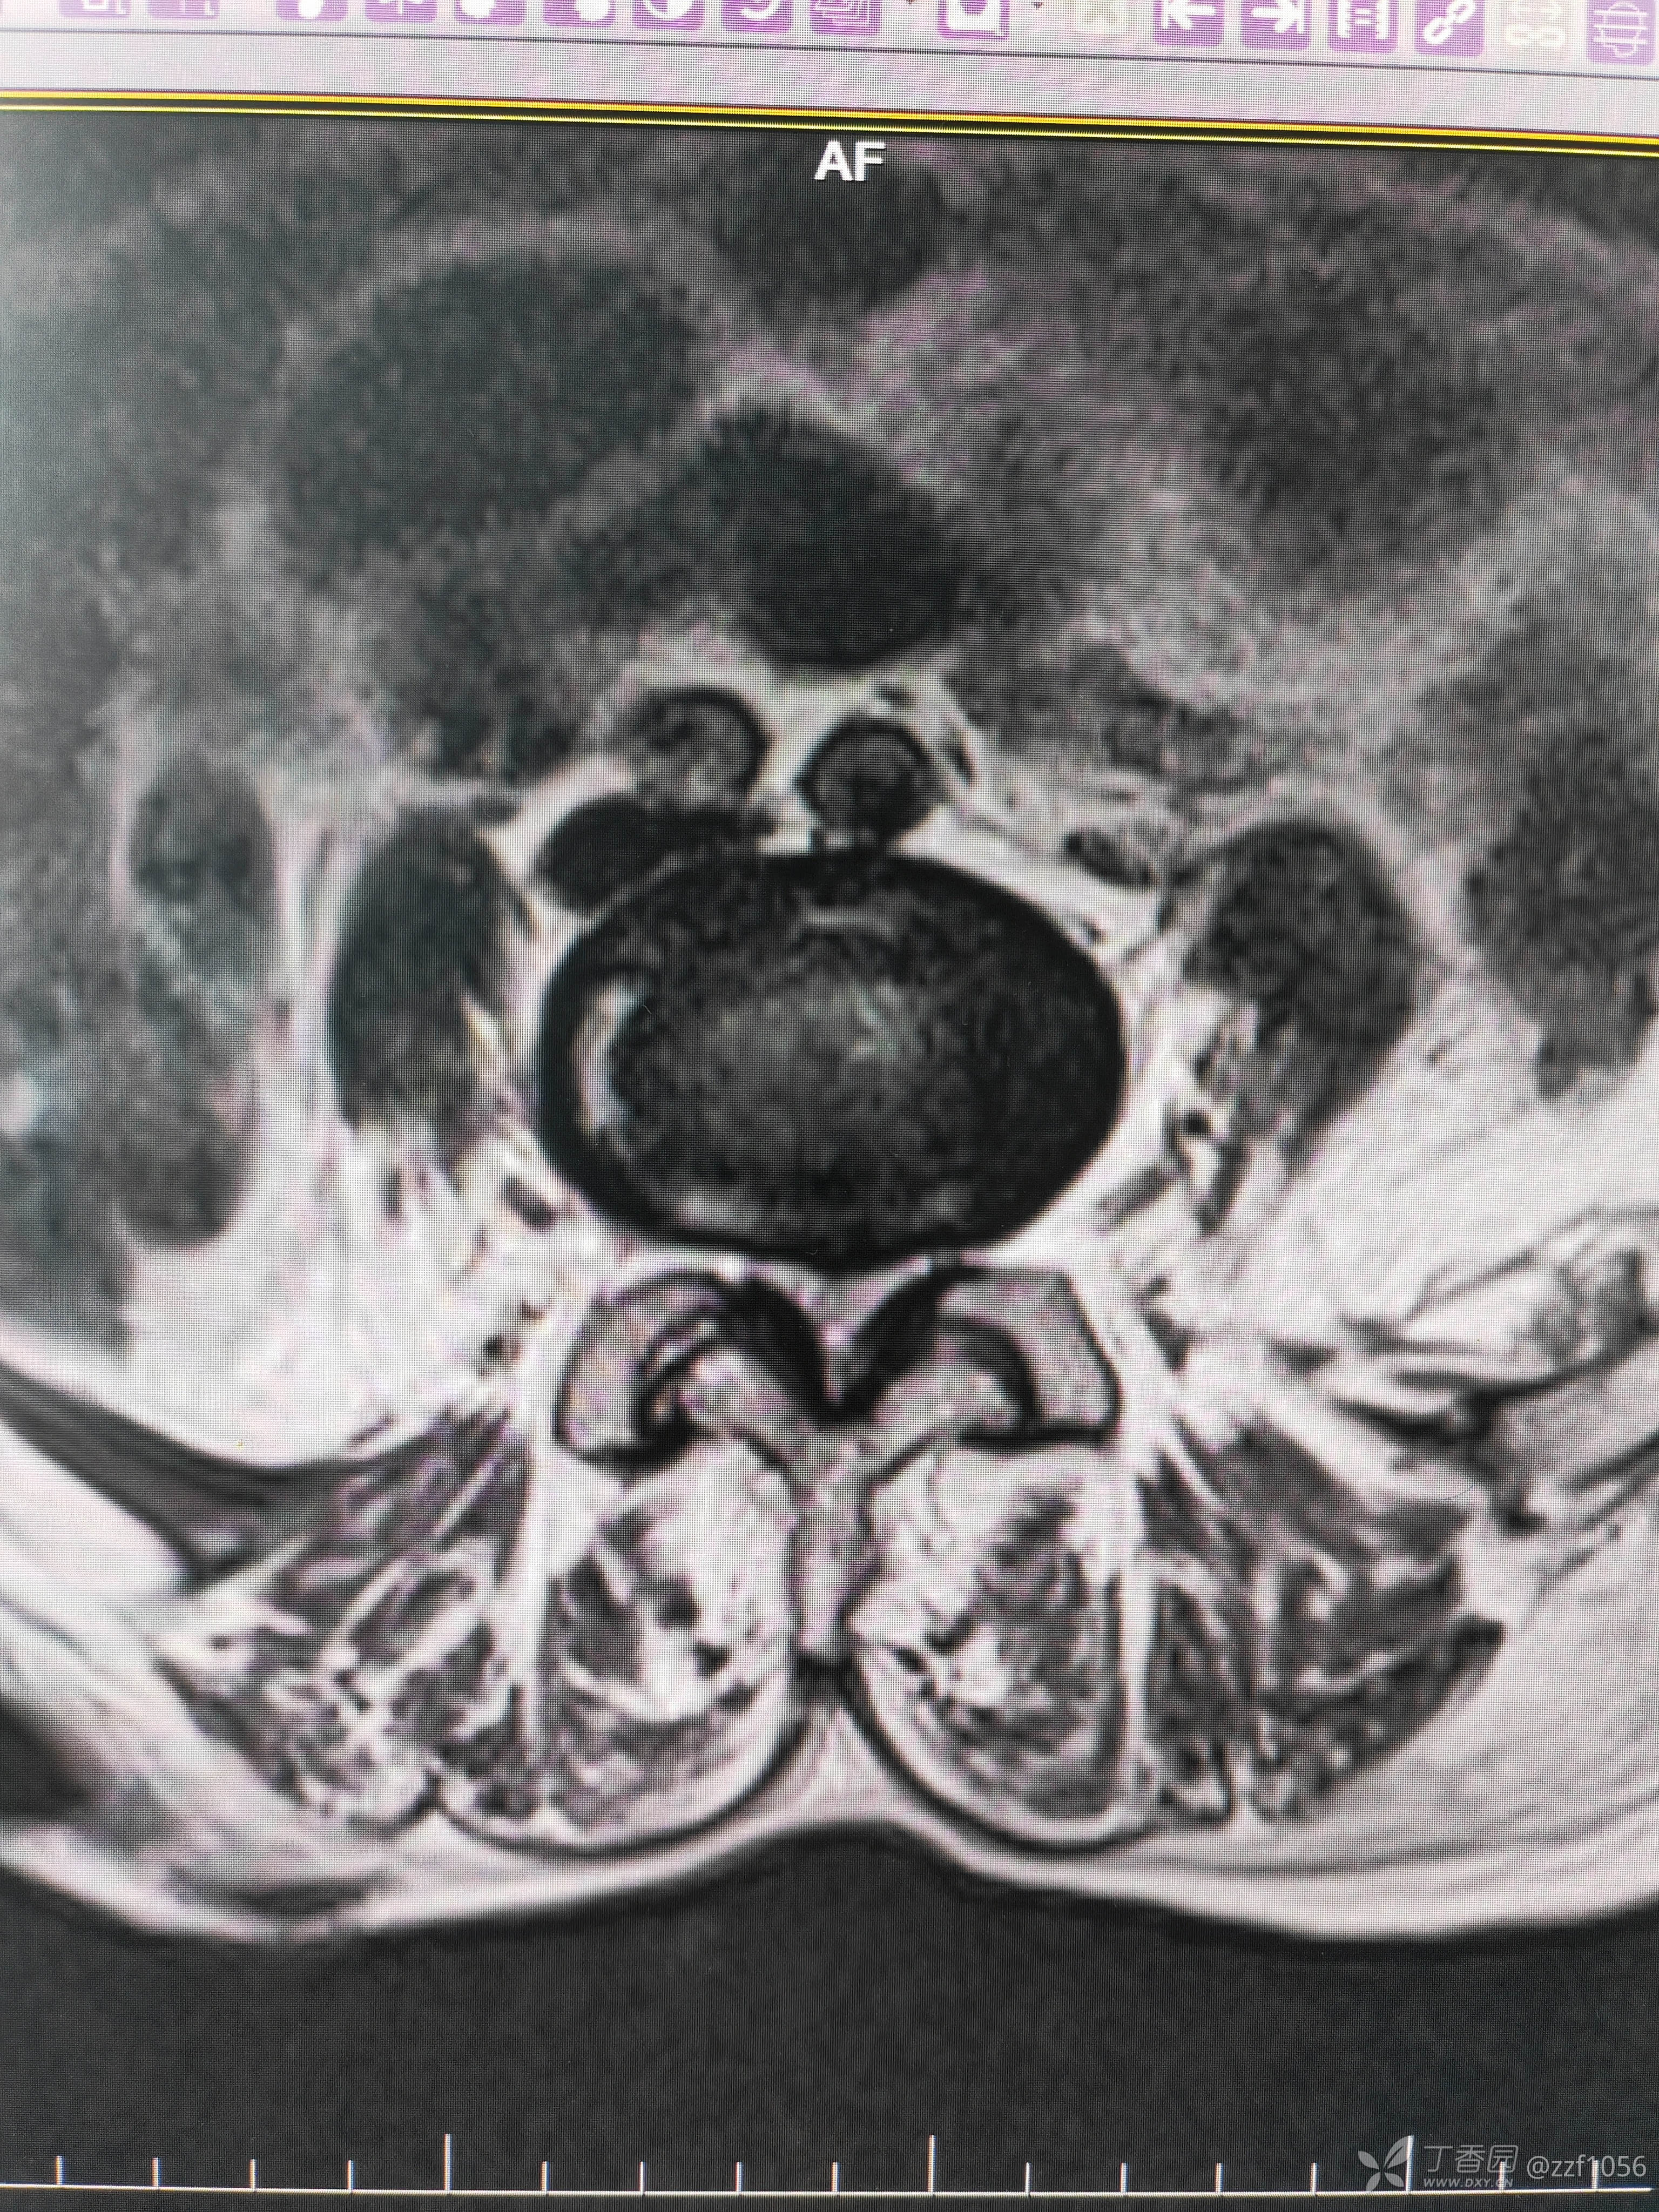

黄韧带肥厚

椎管狭窄

核磁结果L4/5狭窄明显,L5/S1突出存在,仔细查体,高度考虑左下肢L5根症状,其实患者也说不清楚,并且耳背😃